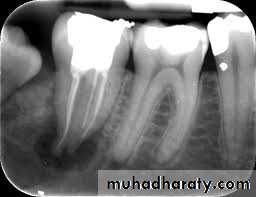

This is the most common reason to remove a tooth. Badly carious teeth that are beyond restoration should be removed . Badly carious teeth result in deterioration of the oral hygiene resulted in bad oral hygiene and bad smell in addition to that sharp edges of the carious teeth leads to repeated ulceration to mucosa in addition to pain during eating and drinking . Untreated teeth with caries may end with pulpitis , periapical pathology etc…2- Server periodontal disease :

Sever and extensive periodontal disease is a common reason for tooth removal , in chronic periodontitis there is excessive bone loss and mobility in the tooth . As a rough guide loss of about half of the normal alveolar bone or extension of pockets to the bifurcation of the roots of posterior teeth and hypermobility of the teeth means that extraction of the involved tooth is necessary . Patient with advanced periodontitis may complains of mild to server throbbing pain in case of development of periodontal abscess .3- Pulp pathology :

4- Apical pathology :

Periapical lesions like periapical abscess , granuloma , cyst. If the teeth fail to respond to all conservative treatment to resolve apical pathology due to technical reasons or other causes such teeth are indicated for extraction .